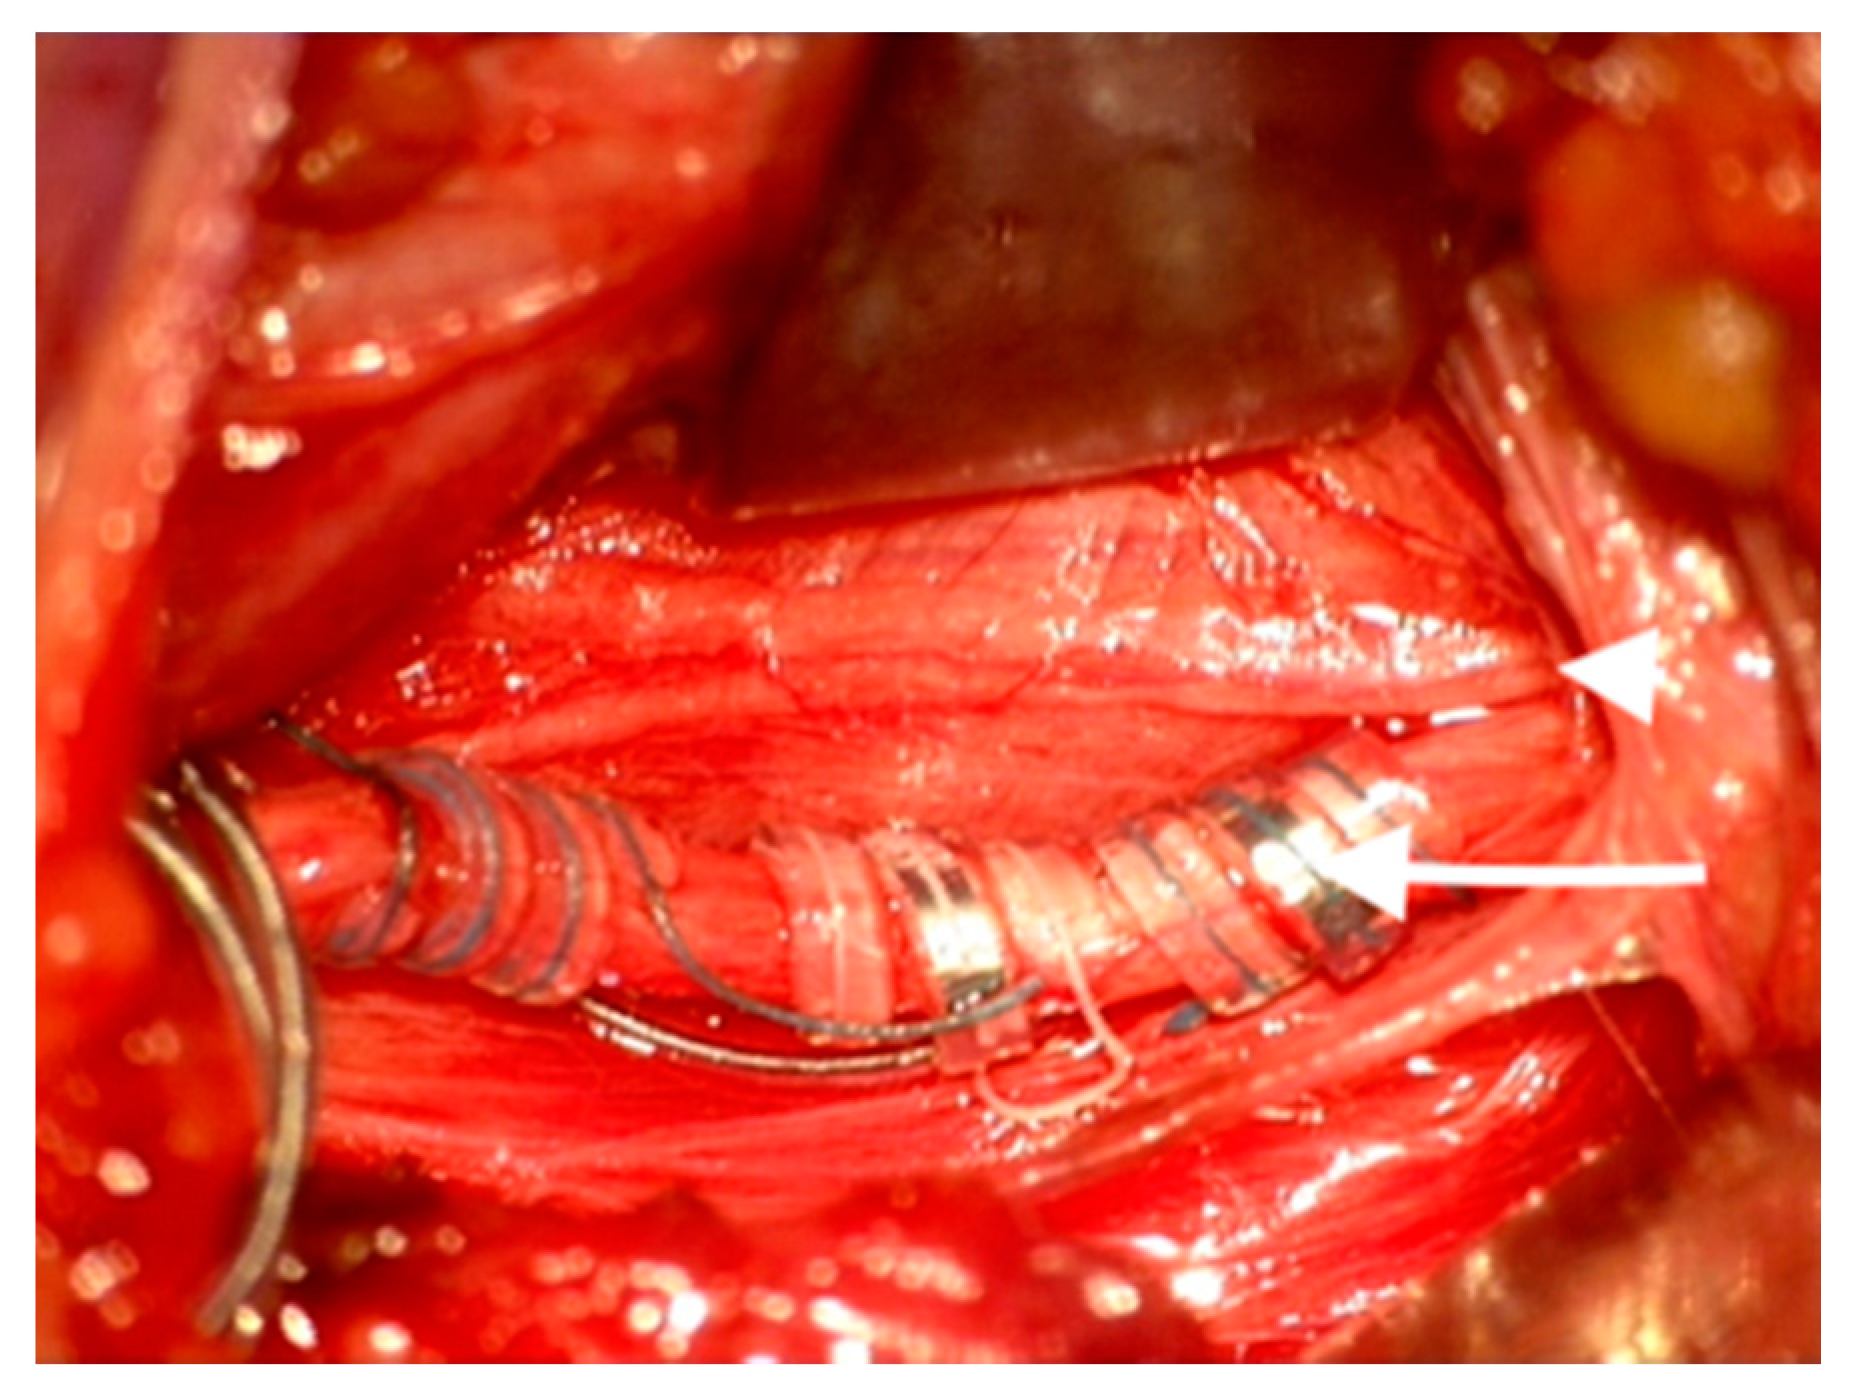

The VNS coils of the VNS Stimulator (AspireSR, model 106, Cyberonics Inc. Houston, TX, USA) were placed around the main vagal trunk, away from the branching point. (Figure 2).

Figure 2. Vagus nerve stimulator (VNS) electrode placed around the main vagal trunk (white arrow) with the aberrant branch displaced medially at the branching point (white arrowhead) on the left side.